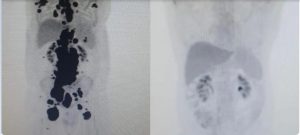

Vanderson Rocha, professor de hematologia, hemoterapia e terapia celular da Faculdade de Medicina da USP e coordenador nacional de terapia celular da rede D’Or, está à frente do caso de Paulo. “Foi uma resposta muito rápida e com tanto tumor. Fico até emocionado [ao ver as duas ressonâncias de Paulo]”, disse Rocha.

“Fiquei muito surpreso de ver a resposta, porque a gente tem que esperar pelo menos um mês depois da infusão da célula. Quando a gente viu, todo mundo vibrou. Coloquei no grupo de professores titulares da USP e todo mundo impressionado de ver a resposta que ele teve”, comemorou o especialista.

Entre os outros 13 pacientes tratados como Paulo, 69% tiveram remissão completa em 30 dias. O primeiro paciente tratado com a técnica na rede pública do Brasil teve resultados parecidos com os de Paulo, mas morreu por um acidente doméstico em casa.